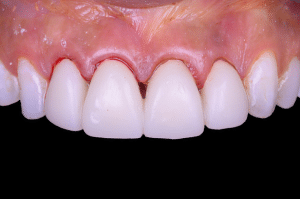

Fig 10

Aspect clinique le jour de la mise en place des prothèses d’usage individuelles.